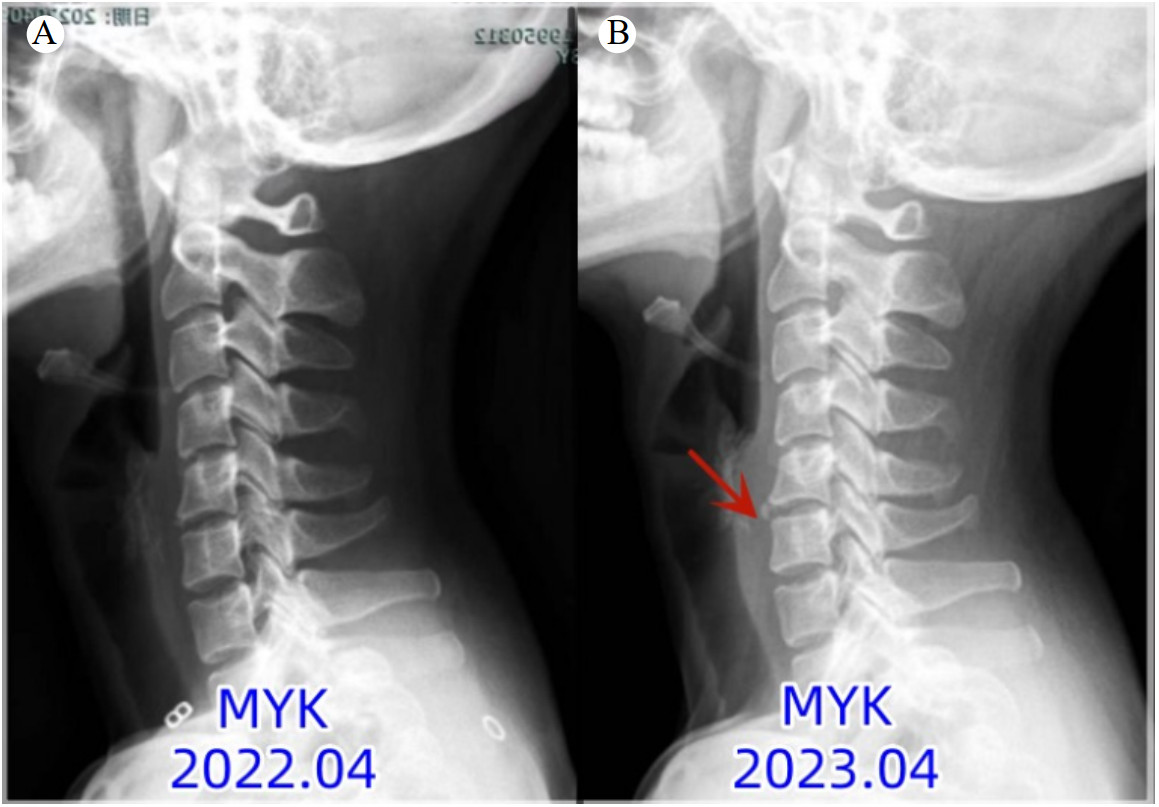

1 病例资料患者,女性,28岁,信息技术程序员,因“颈痛1 d”于6月23日到杭州市中医院就诊。患者自诉1 d前无明显诱因出现颈部疼痛,呈持续性,伴轻度咽部疼痛,无发热、咳嗽,至本院急诊就诊。患者既往有颈痛病史,影像检查见图 1。急诊给予血常规(白细胞、C-反应蛋白均正常)和颈椎CT检查(见图 2A)提示颈椎退变,曲度变直,C5/6前缘骨赘。初步诊断考虑“颈痛,颈肌扭伤”,给予洛索洛芬钠片口服治疗。6月24日患者颈部疼痛明显加剧,无法吞咽食物(吞咽困难),于五官科门诊行喉镜检查未见明显异常,于消化内科门诊就诊,考虑颈痛明显建议先于骨科就诊,未进一步行胃镜等相关检查。颈椎MRI(见图 3A)提示:颈椎椎前水肿积液,考虑“急性钙化性肌腱炎”,给予糖皮质激素(氢化泼尼松龙)、林格氏液静滴,患者自诉颈痛及吞咽困难/疼痛有所好转。6月24~26日连续静脉应用糖皮质激素3 d,患者颈部疼痛及吞咽疼痛明显缓解,改用洛索洛芬钠片继续治疗1周。7月8日于骨科门诊复查颈椎X线(图 2B)提示颈5/6前缘钙化明显缩小(较6月24日),MRI(图 3B)提示颈椎前缘水肿信号消失,颈椎退变。

| 注:A为颈椎曲度变直;B为颈椎退变,曲度变直,C5/6前缘可见增生骨赘 图 1 患者既往颈椎相关影像学检查结果 |

钙化性肌腱炎的自然病程通常分为三期:钙化前期、钙化期、钙化后期;钙化期又分为钙化形成期、静止期和重吸收期[9]。在钙化的吸收阶段,钙化沉积物被炎性细胞吞噬,诱发炎症反应,这是患者最痛苦的阶段[9]。Tezuka等[10]回顾文献总结17例ACTLC患者钙化物影像学吸收现象,发现吸收时间分别为 < 1个月(11例)、1~2个月(4例)、> 2个月(2例);且临床症状并不完全与影像学表现相一致,临床症状的完全恢复需要1~2个月,钙化物的完全消失通常需要3~4周。本病例图 1A显示C5/6前缘未见骨化,属于钙化前期;而图 1B显示钙化,而无相应的临床症状,属于钙化期;图 2A出现典型的临床症状,属于吸收期;在末次随访时,C5/6前缘钙化影几乎完全消失,属于钙化后期。ACTLC为良性自限性疾病,疼痛多在1周达到高峰,2~4周缓解[11]。本病例经过糖皮质激素的治疗,病程持续1周即完全缓解,对ACTLC充分认识的基础上早期应用糖皮质激素能够大大缩短病程,减轻患者痛苦。